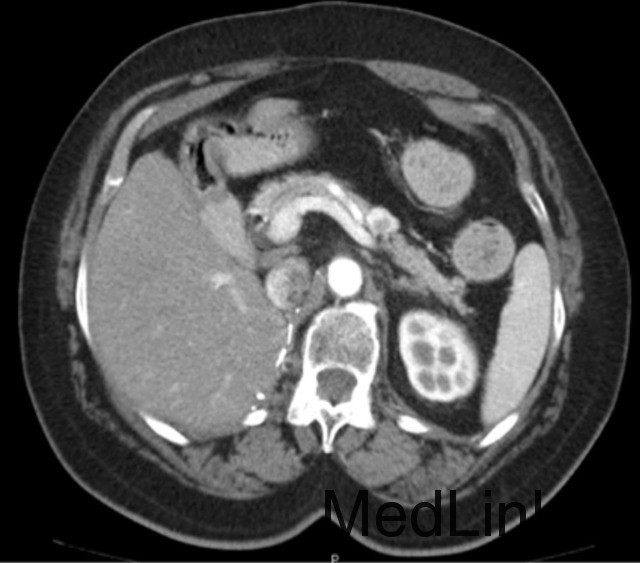

CT 显示在胰腺体上出现 20 mm 占位 (图 a)。MRI 显示在胰体胰尾之间出现 20×13 mm 实性结节,增强 MRI 提示神经内分泌源性 (图 b)。生长抑素闪烁照相显示在胰腺和右侧甲状腺生长抑素受体异常高表达。通过脑部 MRI 检查结果显示为正常,可排除 Von Hippel-Lindau 综合征 (VHLD)。